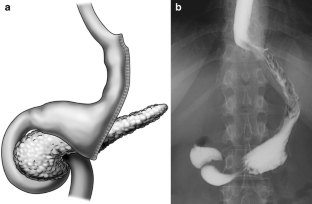

Fig. 1